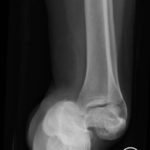

The X-rays were significant for a subtalar dislocation. The calcaneus (red) is laterally displaced with respect to the talar head (orange), and the white lines indicate the normal articular surface. Additionally, there was a talonavicular dislocation, as seen in the fourth image: the talus (green) and navicular bone (purple) overlapping suggests a dislocation. In a normally aligned foot, the boundaries of the two bones create a point of articulation.

Proper diagnosis of talonavicular dislocations require obtaining anteroposterior (AP), lateral, and mortise views of the ankle and foot.3 The utility of computed tomography (CT) in diagnosis has also been discussed. One study reported that 44% of patients who received CT for subtalar dislocation had a treatment plan differing from that based on plain film findings.4 Specifically, CT identified fractures that were not visible on plain films as well as intraarticular debris requiring evacuation in an effort to promote proper healing and function.